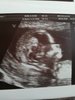

Już po wizycie. Wszystko pięknie! Dzidziol tańczył jak szalony

Co do płci... Moj lekarz powiedział, ze z tego co teraz widzi to moze byc i chłopczyk

powiedzial, ze jeszcze za wczesnie, narzady rozrodcze w tej chwili wygladaja prawie identycznie i u chlopca i u dziewczynki. Płeć powie za miesiąc